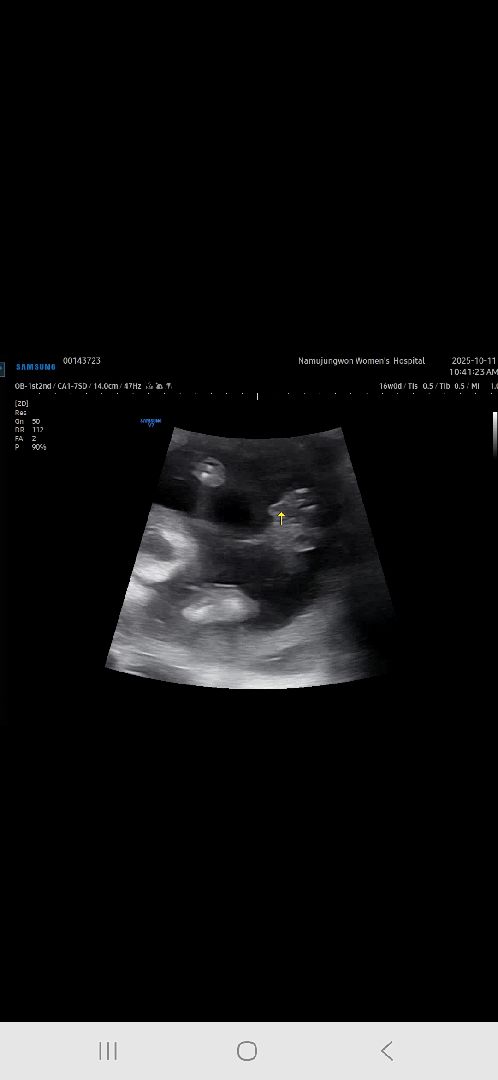

16주차 성별보고왔는데 반전 없겠죠?

정확하게 다리사이는 아닌것같은데 의사선생님이 생식기고 아빠닮았네요~ 라고 하셔서ㅋㅋㅋㅋㅋㅋ 다 딸이라고 해서 딸인줄알았다가 완전 반전